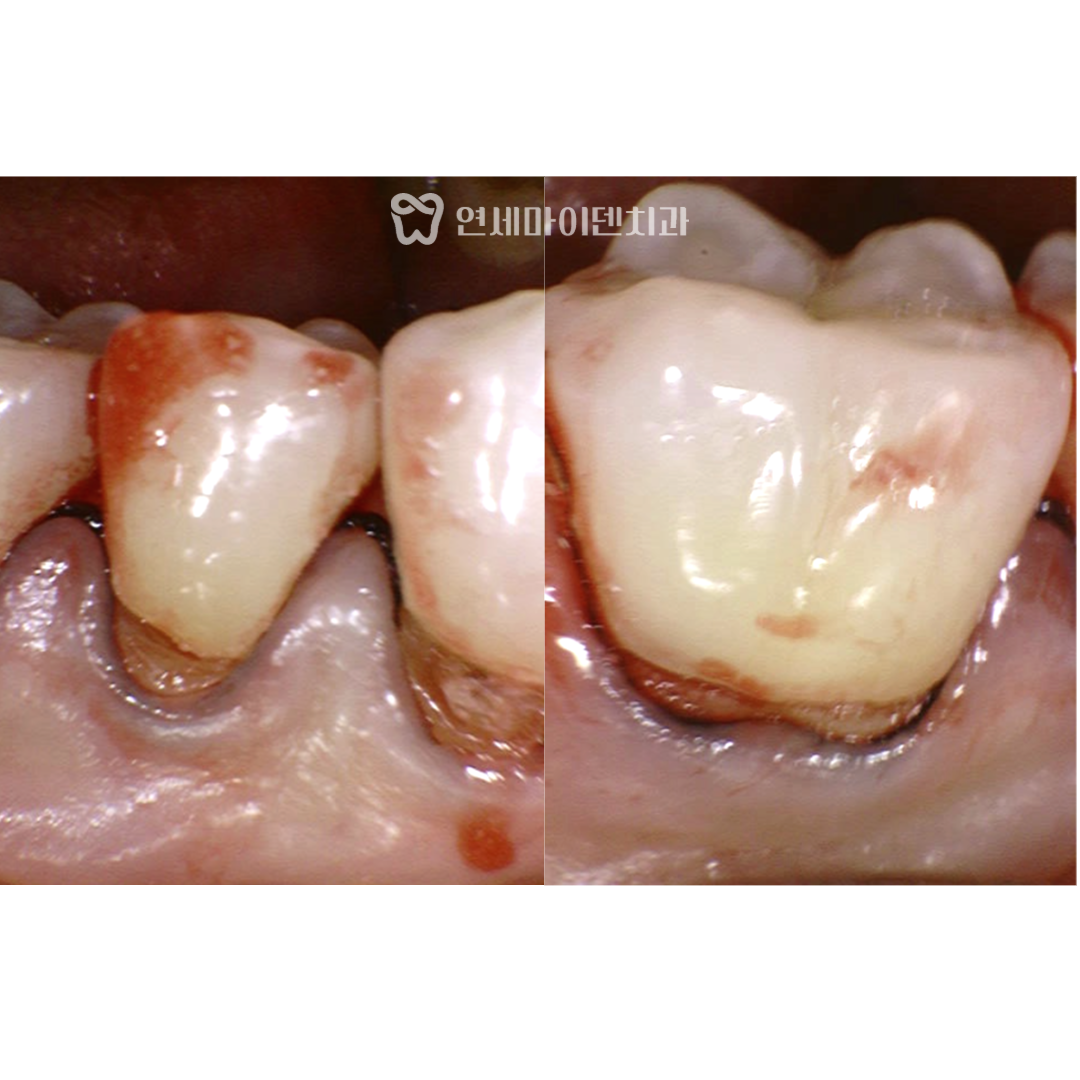

치경부 마모증, 레진 치료가 필요한 이유

신경이 괴사된 치아 외에도

반대쪽 치아에서도 치경부 마모증이 진행되어 있었습니다.

다행히 이 부위는 신경 괴사까지는 진행되지 않았지만,

방치할 경우 같은 결과로 이어질 수 있기 떄문에

사전에 레진 수복 치료를 진행했습니다.

치경무 마모증에 대한 레진 수복은 단순한 메음이 아니라

자연스러운 모양과 매끄러운 경계선 처리가 중요합니다.

형태가 부자연스럽거나 경계가 날카로운 경우,

잇몸에 오히려 자극이 생기고 염증이 악화될 수 있습니다.

따라서 레진 수복은 미세한 조정 기술과

세심한 테크닉이 매우 중요한 치료라고 할 수 있습니다.

이번 치료에서도 정밀한 수복을 통해

잇몸과의 조화를 이루도록 치료를 완료해드렸습니다.